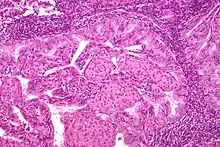

Pathology

- Epithelial tumors. For mesenchymal tumors, please see the uterine sarcomas page

- Most are well-differentiated, with proliferation of endometrial glands without intervening stroma

- Endometrial hyperplasia is thought to be a precursor lesion developed with unopposed estrogen and genetic events

- Simple vs complex hyperplasia based on glandular architecture

- Cytologic atypia increases risk of progression to carcinoma (complex atypical hyperplasia risk ~30%)

- Cells show microsatellite instability, PTEN, and k-ras mutations

- Papillary serous (1-5%)

- Complex papillary architecture, similar to papillary serous CA of ovary

- Presence of psammoma bodies

- Marked nuclear atypia

- Believed to transform from endometrial surface epithelium